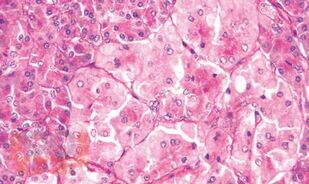

Патоморфологическая диагностика опухолеподобных образований поджелудочной железы

В книге изложены основные представления об этиологии, о клинических проявлениях и морфологической картине различных опухолеподобных изменений экзокринной и нейроэндокринной части поджелудочной железы. Данная работа представляет собой первую попытку в отечественной литературе систематизировать и осветить различные формы опухолеподобных заболеваний поджелудочной железы.